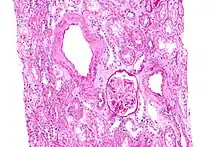

L’amylose rénale est de loin la plus précoce et la plus fréquente des complications

La substance amyloïde de la maladie périodique est formée de fibrilles identiques à la protéine de l'amylose AA, et elle intéresse de manière diffuse la paroi de toutes les artérioles, sauf celles du système nerveux central ; cette répartition est dominée par la localisation rénale..

Son évolution passe par deux phases principales. Le début est asymptomatique, il s'agit d'une protéinurie modérée, de durée moyenne de 3 à 4 ans. Son apparition au cours de la maladie périodique constitue une très forte présomption d’amylose, et cette protéinurie doit être recherchée au moins une fois par an[31].

La phase néphrotique est caractérisée par l’apparition d’un syndrome néphrotique clinique et biologique. La confirmation histologique peut être apportée par la biopsie rénale, la biopsie rectale (positive dans 75 à 85 % des cas), voire par la biopsie médullaire.